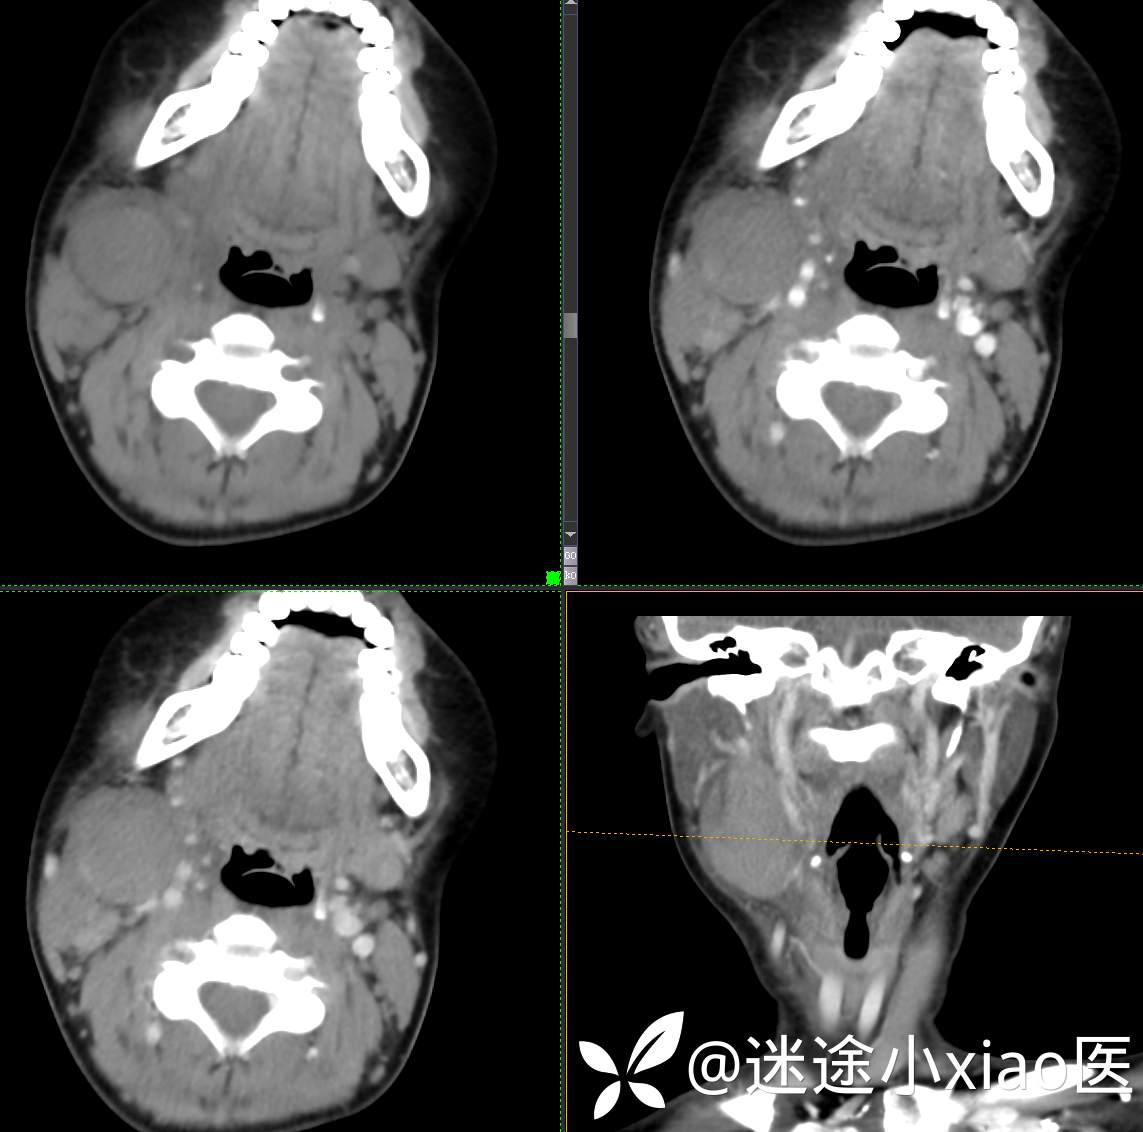

头颈组16:青少年女性,发现右颈部肿物半月余,感染?肿瘤?

主 诉:发现颈部肿物半月余

现病史:患者半月余前无明显诱因下发现右颈部肿物,大小4.2*2.1cm,局部无红肿,皮温正常,有压痛,感头晕头痛,无其他不适。查甲状腺及颈部淋巴结B超提示:双侧甲状腺多发结节;右侧多发肿大淋巴结。初步诊断为“淋巴炎”,予“头孢类”抗生素抗感染治疗12天(具体药物不详),自觉肿块胀痛缓解,头晕头痛症状仍存。